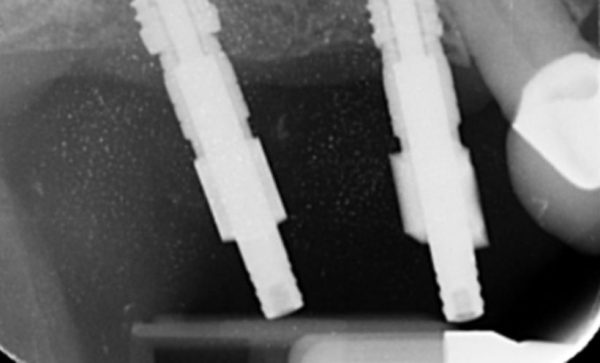

Before Xray - Abacus Dental

After Xray -Abacus Dental